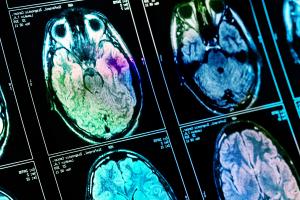

Une activité anormale dans un circuit cérébral particulier, qui provoque l’anorexie chez un modèle animal (Visuel Adobe Stock 427281694)